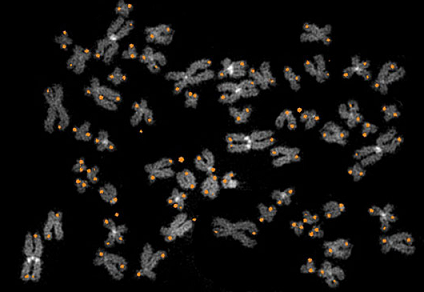

全基因组测序鉴定儿童恶性白血病基因重排